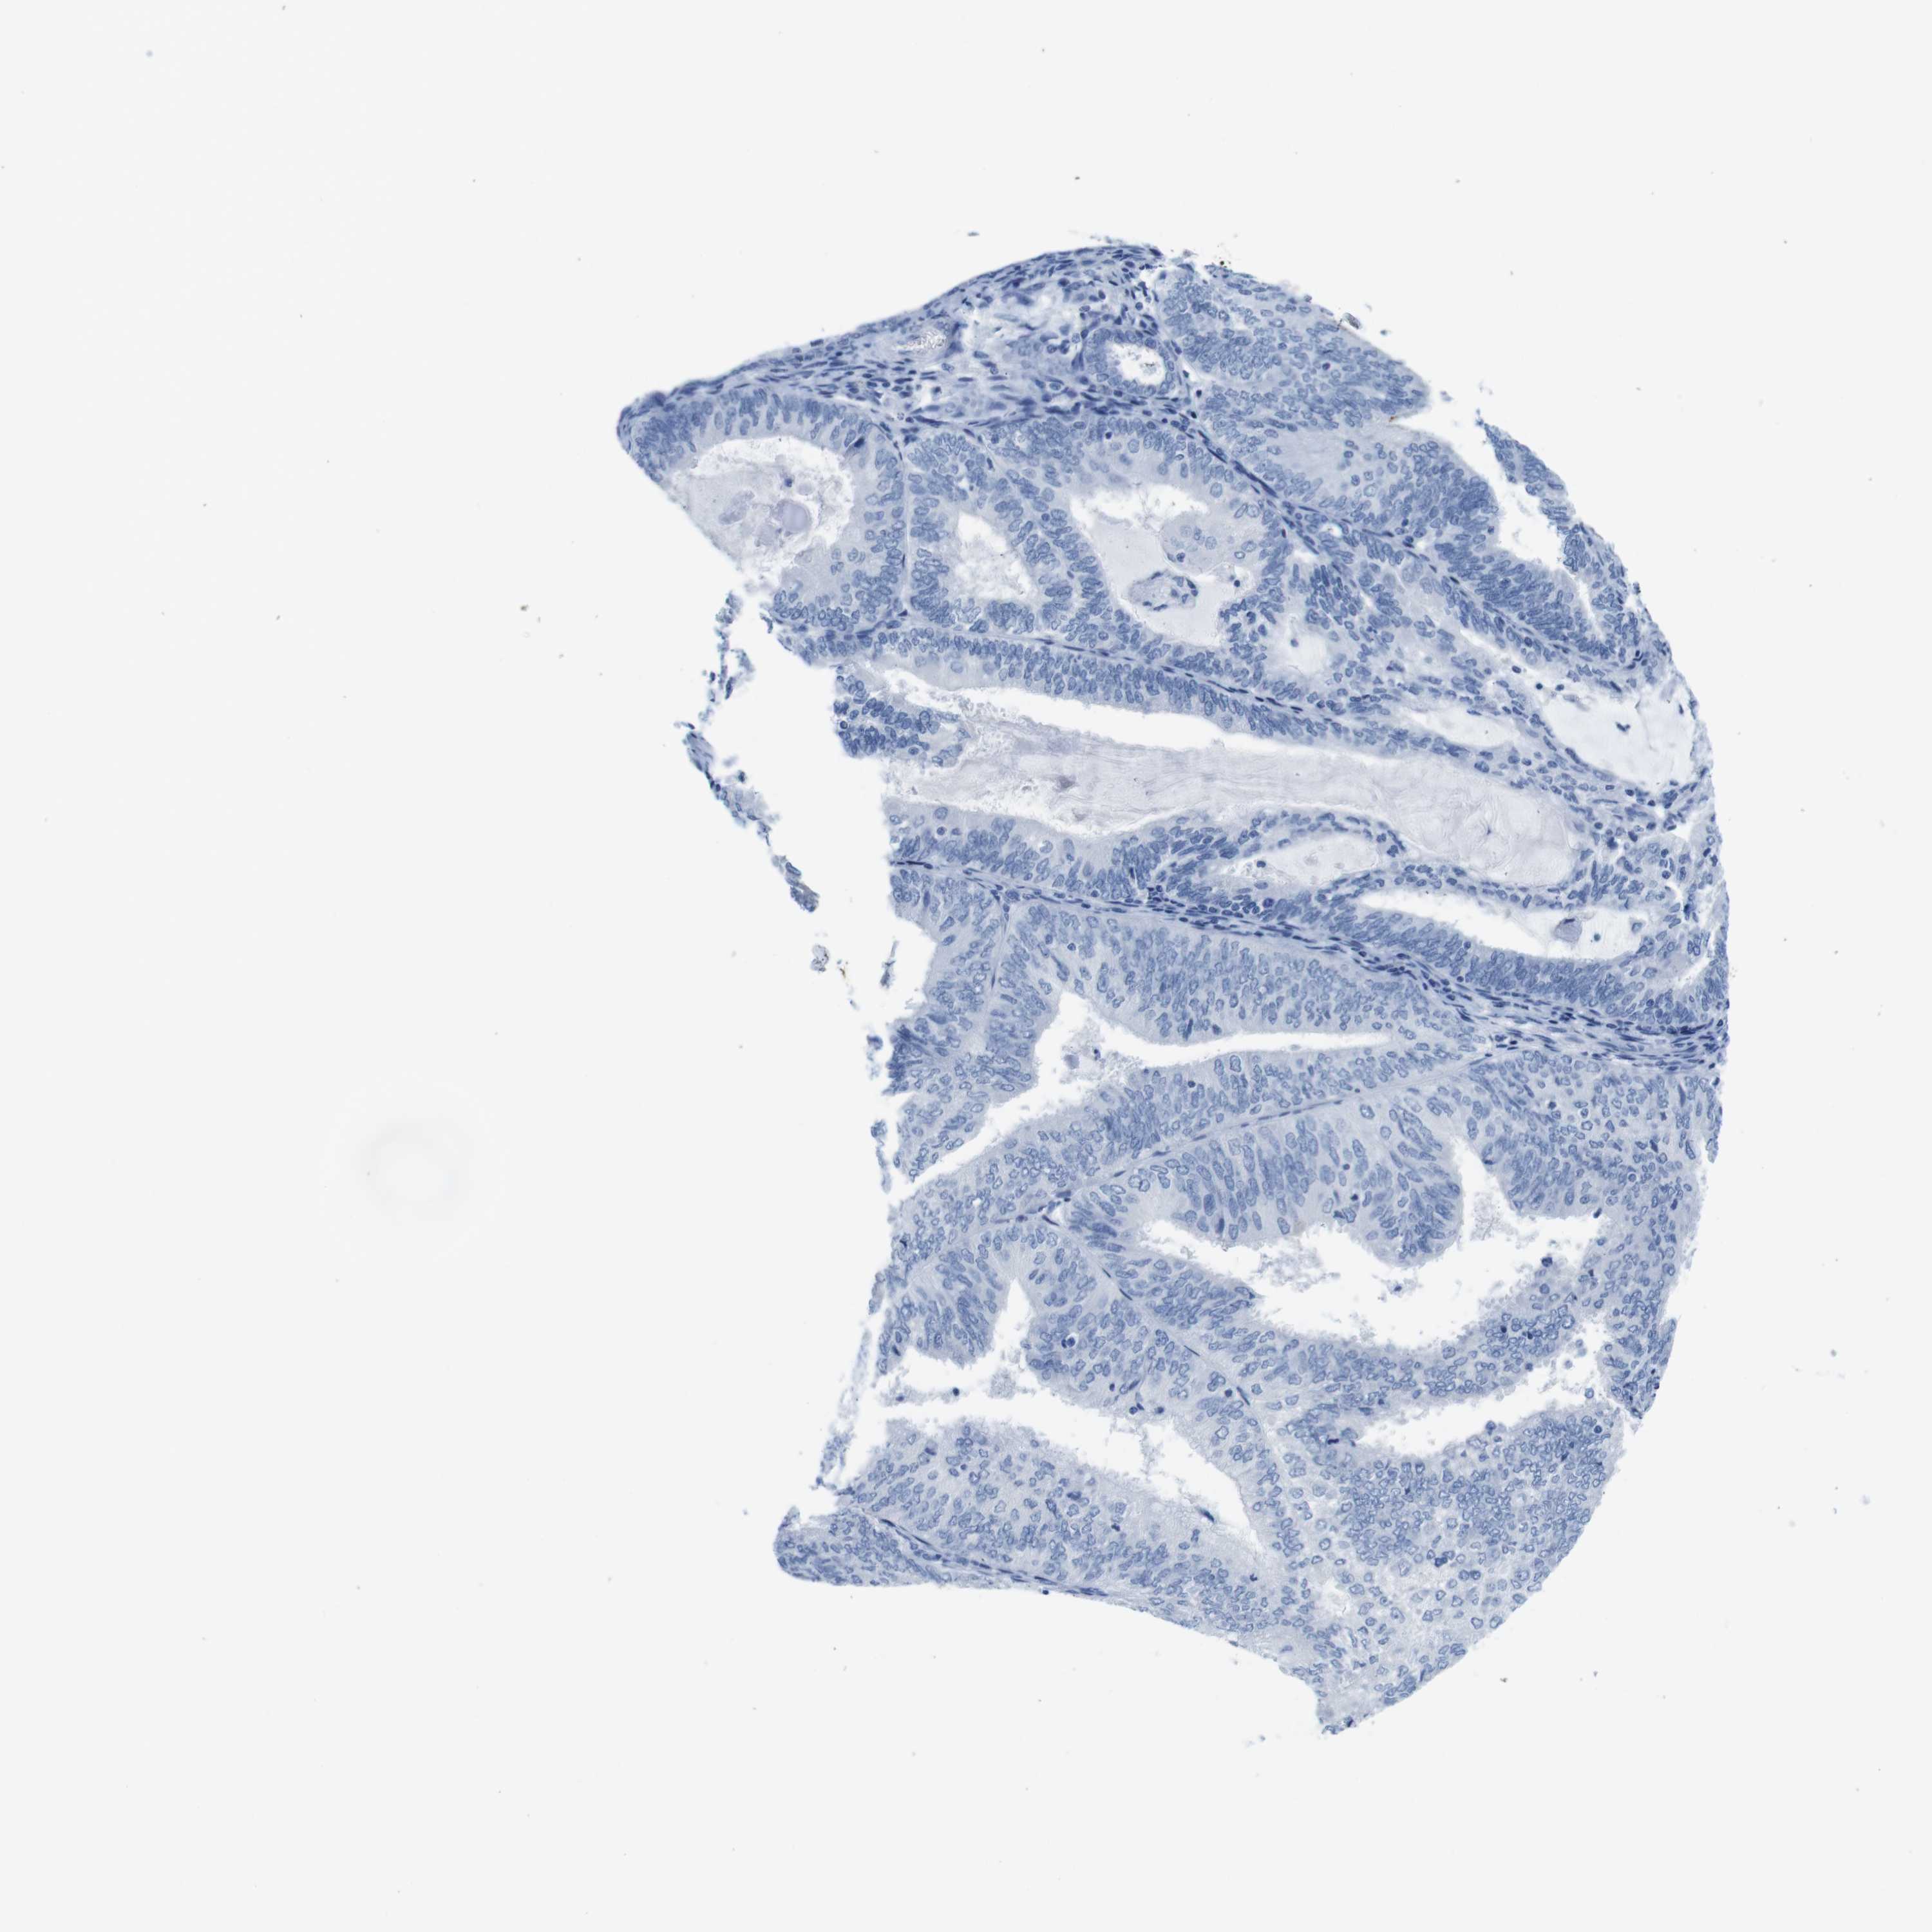

ENDOMETRIAL CANCER - Protein expressioni

A mouse-over function shows sample information and annotation data. Click on an image to view it in a full screen mode. Samples can be filtered based on level of antibody staining by selecting one or several of the following categories: high, medium, low and not detected. The assay and annotation is described here.

Note that samples used for immunohistochemistry by the Human Protein Atlas do not correspond to samples in the TCGA dataset.

Antibody stainingi

Antibody staining in the annotated cell types in the current human tissue is reported as not detected, low, medium, or high, based on conventional immunohistochemistry profiling in selected tissues. This score is based on the combination of the staining intensity and fraction of stained cells.

Each image is clickable and will lead to virtual microscopy that enables deeper exploration of all samples and also displays staining intensity scores, fraction scores and subcellular localization as well as patient and tissue information for each sample.

Antibody HPA039061

Antibody HPA039062

Antibody CAB015442

Antibody CAB022600

Staining

High

Medium

Low

Not detected

Intensity

Strong

Moderate

Weak

Negative

Quantity

>75%

75%-25%

<25%

None

Location

Nuclear

Cytoplasmic/membranous

Cytoplasmic/membranous,nuclear

Adenocarcinoma, NOS